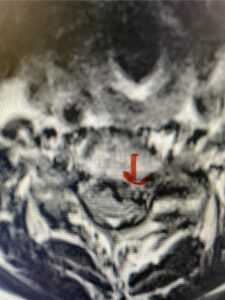

In this next case, this patient is a 47 year-old female who presents with intractable low back pain with severe pain, numbness, and weakness in the right lower extremity that had gotten progressively worse over a year. The patient had failed conservative management including physical therapy and epidurals. She was noted to have ⅘ weakness of plantar flexion. MRI demonstrated a large right L5-S1 disc herniation with severe compression of the descending right S1 nerve root (Fig 3). It was decided to perform a right L5-S1 hemilaminectomy for removal of the disc fragment and decompress the S1 nerve root. When you expose the disc, one must be certain to release any anterior adhesions to the nerve root in order to prevent a dural tear during retraction of the nerve root. It is also important to make sure during exposure and you finally encounter the dura after removing the ligamentum and fat, to make sure you are looking at the nerve root and not the main trunk of the thecal sac because if you don’t you can avulse or damage the nerve root if you retract the wrong structure.

Fig. 3a: Sagittal and axial T2-weighted lumbar MRI images demonstrating large right L5-S1 disc herniation (red arrows)

Fig. 3b